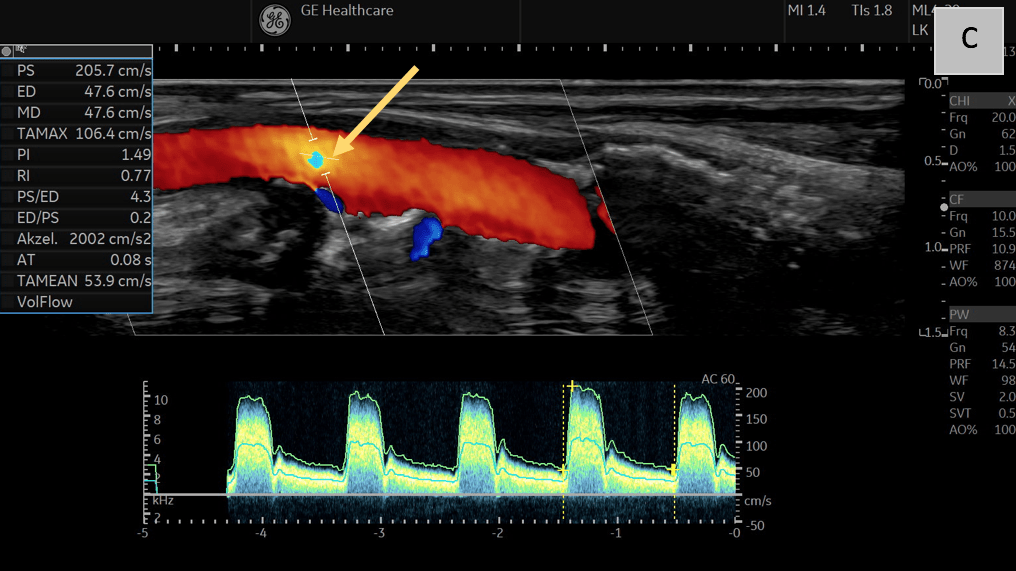

C: Triplex, B-Mode, and Duplex imaging with color coding and pulsed wave Doppler reveal significantly increased systolic flow velocities (>200 cm/s) in the CCA, accompanied by aliasing in the region of luminal narrowing (yellow arrow) caused by echogenic plaque formation.

Triplex ultrasound integrates B-Mode, Color Doppler, and Spectral Doppler to provide comprehensive structural and hemodynamic data, including flow velocity quantification and the detection of microvascular activity (Fig. C). Furthermore, tomographic three-dimensional (3D) ultrasound uniquely enhances understanding of vessel anatomy (Fig. D) and serves as an innovative adjunct imaging modality.

• Comprehensive Hemodynamic Assessment with Triplex Ultrasound: Triplex ultrasound combines B-Mode (structural imaging), Color Doppler (flow visualization), and Spectral Doppler (velocity quantification), providing both anatomical and functional data. This is essential for identifying stenotic lesions, flow velocity changes, and areas of turbulent flow associated with high-risk plaques.